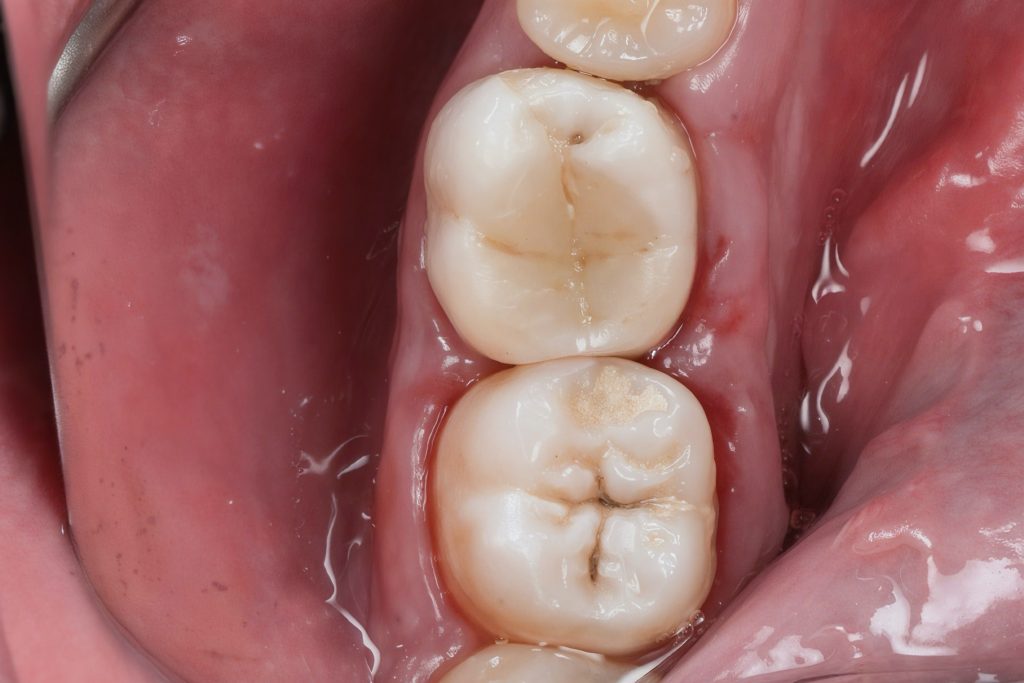

Rubber dam isolation was achieved to prevent contamination (Fig 2). Conservative access cavity preparation was performed under a dental microscope to maintain structural integrity and preserve pericervical dentin.

- Fig 2: Rubber dam isolation for aseptic workflow.